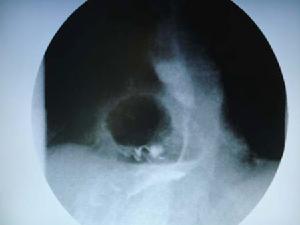

(1)食管鋇劑造影:食管結核病人若因吞咽困難而作X 線鋇劑造影檢查,其X 線表現缺乏特異性。此時的診斷思路如果僅僅局限於多發病、常見病上,易誤診為食管惡性腫瘤。有時食管結核的X 線表現甚至可能正常,往往造成漏診。食管結核的鋇劑造影檢查可以發現下列徵象:

①潰瘍型幾乎都發生在食管中段,主要表現為食管管腔潰瘍,可見龕影,但也並非所有病人都能見到潰瘍所形成的龕影這一徵象。由於瘢痕收縮及周圍組織粘連而使管腔輕度狹窄或正常,黏膜紋理粗亂不規則,管壁輪廓可不規則呈鋸齒狀,但管壁僵硬不明顯,仍有一定的擴張度,鋇劑可順利通過。

②增殖型多見於食管中段,其次為下段。X線檢查多顯示程度不等的管腔狹窄,為側壁局限性充盈缺損,大小不一,管壁有一定彈性,鋇劑通過緩慢,而無梗阻。在充盈缺損附近有軟組織腫塊影,為增厚的管壁或腫大之淋巴結,病變區域的黏膜紋理可以正常,或變形甚至完全消失。有軟組織腫塊形成,表現為雙邊陰影,外側的邊緣系因鋇劑附著於黏膜而形成,內側邊緣因管壁肥厚隆起而形成。

(5)X 線鋇劑造影檢查:食管結核食管腔有充盈缺損和潰瘍,或黏膜呈蟲蝕

樣改變,管壁稍僵硬,縱隔淋巴結結核壓迫食管所致充盈缺損,多呈弧形,局部黏膜平整,附近有軟組織腫脹影或病變周圍結核鈣化影;而食管癌管壁不整,僵硬,黏膜明顯破壞,充盈缺損明顯且不規則。